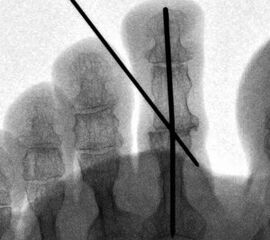

• Belastete Aufnahmen des Fußes in zwei Ebenen (dorso-plantar und lateral) sind hilfreich um das frontale und sagittale Alignement der Zehen zu beurteilen. Zudem ist auf eine eventuell bestehende Luxation bzw. Subluxation des MTP-Gelenkes zu achten.

• Persistierende Fehlstellungen sind der häufigste Grund für Patientenunzufriedenheit 123. Diese können sowohl in der sagittalen, frontalen und transversalen Ebene auftreten.

• Unzureichende Knochenresektion und die persistierende Spannung um Bereich des PIP-Gelenkes kann zu einem Rezidiv der Deformität führen. In diesem Fall ist eine weitere Knochenresektion erforderlich. Zur besseren Stabilisierung können zwei K-Drähte für die Dauer von 4-5 Wochen verwendet werden.